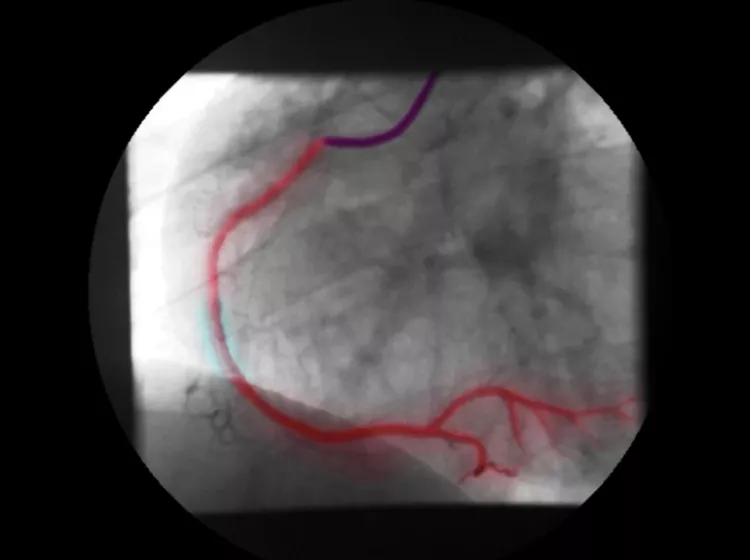

Türk sanat müziğinin usta ismi Muazzez Abacı, geçirdiği kalp krizi sonrası anjiyo olmuş, ardından yoğun bakımda yaşam mücadelesi vermişti. Menajeri Taner Budak’ın açıklamasına göre, anjiyo sırasında kullanılan kontrastlı sıvı böbrek yetmezliğine ve ciğerlerde su toplanmasına yol açtı. 78'inci doğum gününde yaşamını yitiren Abacı'nın ölüm nedeni olarak “kontrastlı sıvı” şüphesi gündeme geldi. Hürriyet'in haberine göre;